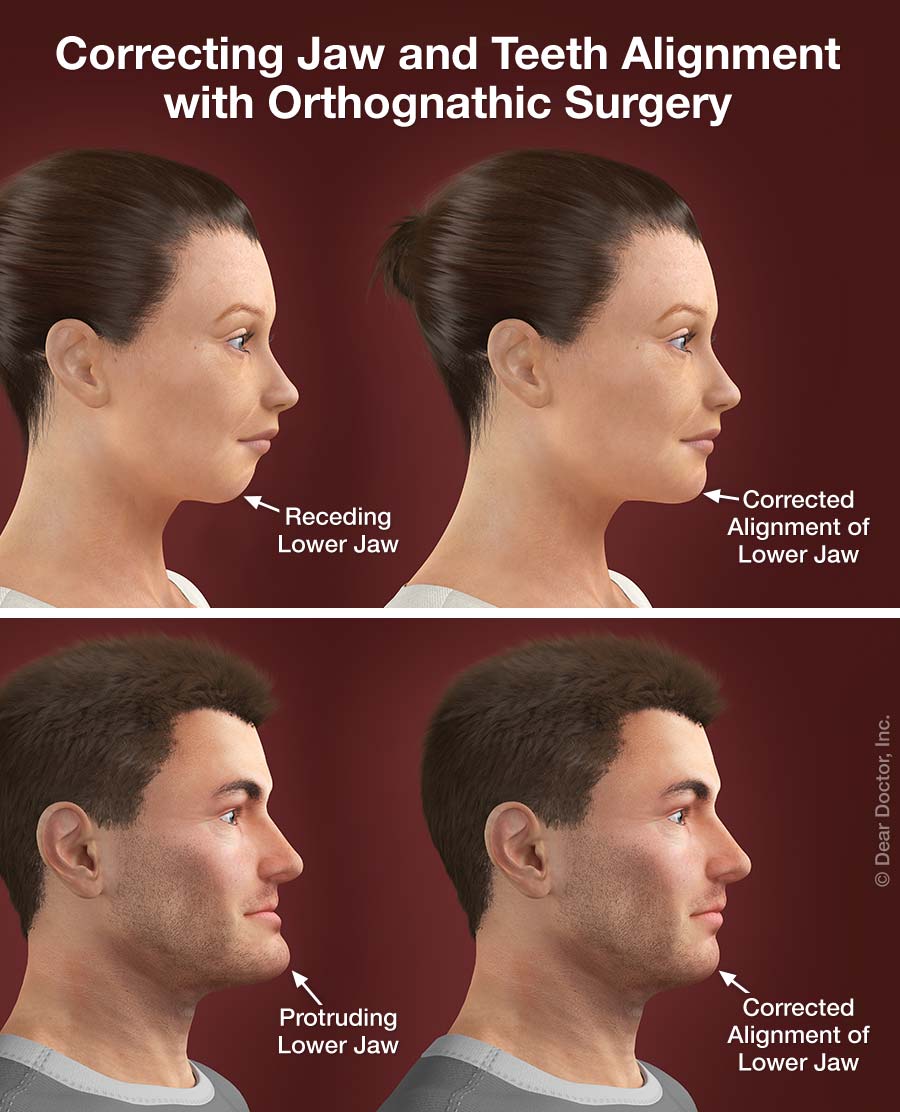

In Depth: What Is Orthognathic Surgery And Would You Benefit From It

In Depth: What Is Orthognathic Surgery And Would You Benefit From It

Types Of Surgical Orthodontics (Orthognathic Surgery)